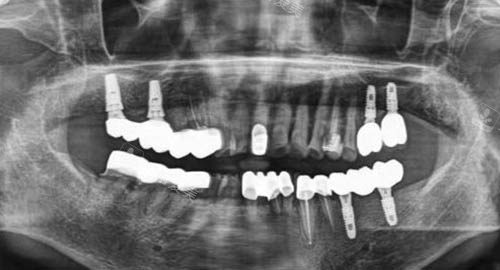

多颗牙齿种植ct

而在种植牙领域,乐美口腔更是有着出色的表现。

可靠的医生团队会根据患者的口腔状况、骨质条件等制定个性化的种植方案,采用较高的种植技术和优质的种植体,让患者能够拥有如同真牙一般的咀嚼体验。